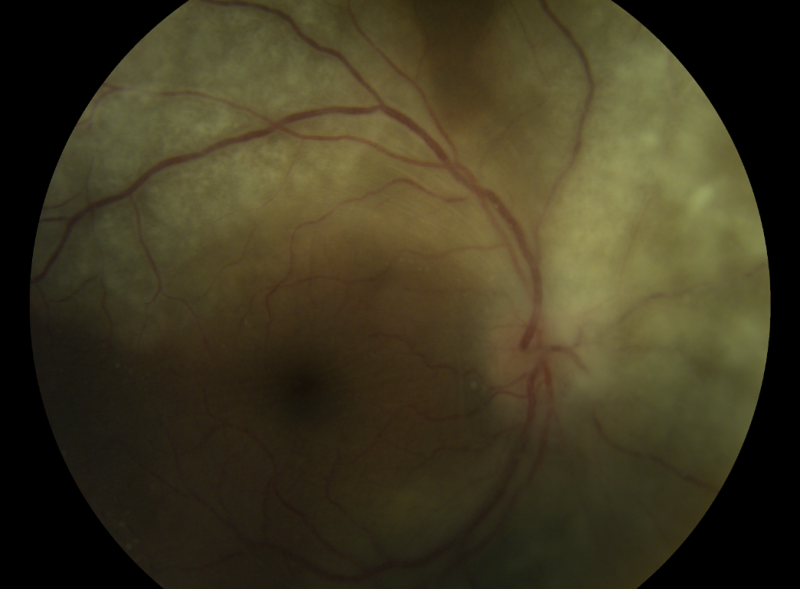

Syphilis is known as the Great Imitator as systemic manifestations vary. Ocular manifestations can affect any part of the eye, with syphilitic uveitis being the most common.

| Uveal Tract | Iritis, iridocyclitis, iris nodules, multifocal choroiditis, Posterior Placoid chorioretintis (typical), round viteous floaters just in front of the retina |

Images of posterior placoid chorioretinitis are available at https://imagebank.asrs.org/discover-new/files/1/25?q=Posterior%20Placoid%20Chorioretinitis